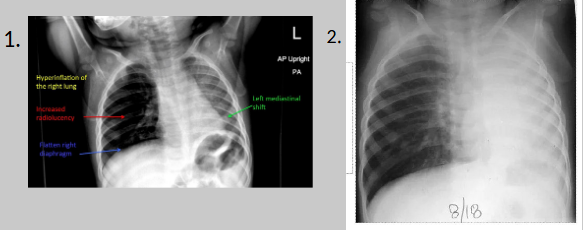

What disorder involves partial or complete collapse of a lobe of lung due to diminished air in the lung?

atelectasis

Where: atelectasis

entire lobe of a lung

Why: atelectasis

secondary condition to:

bronchial obstruction caused by a foreign body

trauma

neoplasm

excessive mucus secretions

RA: atelectasis

a localized increase in density appearing as thin streaks or plates — “plate like atelectasis” to lobar collapse — displacement of lobar fissures

PT presents with difficulty breathing and a productive cough

What pathology is present?